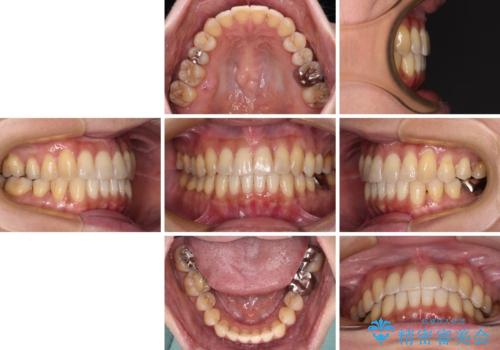

インビザラインで歯列を移動する前に、上顎前歯をワイヤー矯正で整え、その後上下歯列をインビザラインにて矯正治療を行うこととしました。

舌側転位している側切歯特有の、切縁の位置が不揃いであったり、根元が内側に引っ込んだ状態であったりという、インビザライン独特の仕上がりになることなく、きれいに整った歯列とすることができました。